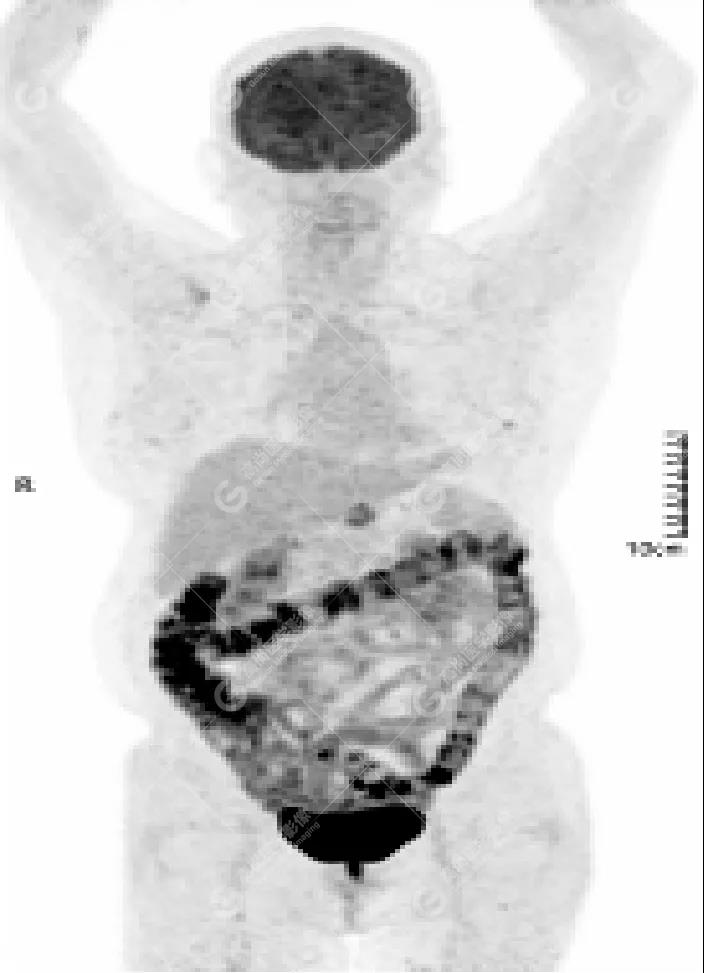

女性 67歲 因背痛查體,糖尿病11年。腫瘤標(biāo)記物:CEA 6.4↑,AFP、CA125、CA199正常。外院MR檢查:胸11椎體-附件左份異常信號,增強環(huán)狀強化,骨原發(fā)?轉(zhuǎn)移?感染?PET/CT影像圖

胸椎溶骨性骨質(zhì)破壞,F(xiàn)DG環(huán)狀代謝增高,SUVmax為4.0。

左側(cè)乳腺一軟組織結(jié)節(jié),F(xiàn)DG代謝增高,SUVmax為2.6。

最終診斷:左側(cè)乳腺癌伴胸椎單發(fā)骨轉(zhuǎn)移。